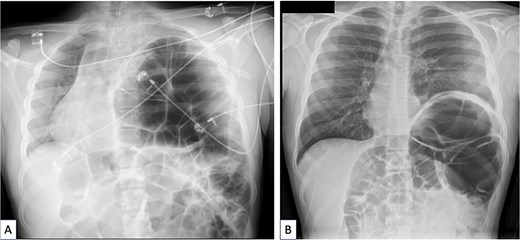

An 18-year-old male originally from Egypt presented to the emergency department with severe abdominal pain suggestive of bowel obstruction. Over the preceding 10 days, he had experienced recurrent non-bilious vomiting, and bowel movements had ceased for 48 h. Since childhood, he had suffered from frequent constipation and had developed chronic abdominal pain during the past year. He had never engaged in sports, particularly endurance activities, and had taken no chronic medication other than laxatives. Physical examination revealed a markedly distended abdomen and absence of breath sounds on the left side. Contrast-enhanced chest and abdominal computed tomography (CT) demonstrated a mesentero-axial sigmoid volvulus with a characteristic “whirl sign,” without evidence of perforation (Fig. 1A and B). The most distended segment of colon had migrated into a large left diaphragmatic eventration, causing mediastinal shift and complete left lung atelectasis (Figs 1C and 2A). Laboratory tests showed no inflammatory response. Under general anesthesia, an initial bedside endoscopic decompression achieved partial detorsion, requiring a second successful endoscopic procedure. Owing to the presence of megacolon and marked mesenteric laxity, the risk ofrecurrence remained high, and surgical management was indicated. Due to organizational constraints, a two-step surgical strategy was adopted. First, an open sigmoidectomy with mechanical end-to-endcolorectal anastomosis was performed. Before thoracic correction, dynamic thoracic magnetic resonance imaging confirmed persistent massive eventration (Fig. 3A), with major mediastinal displacement and absence of contractile activity of the left hemidiaphragm. Pulmonary function tests showed an forced expiratory volume in one second at 71% of predicted (decreasing to 64% in the supine position) and a vital capacity of 74%. Two months later, diaphragm plication reinforced with prosthetic mesh was performed through a video-assisted lower lateral mini-thoracotomy. Intraoperative findings confirmed a massive eventration leaving minimal space for the compressed left lung (Fig. 3B). The diaphragm was extremely thin—~1 to 2 mm—appearing nearly transparent after incision (Fig. 3C). Postoperative recovery was uneventful, except for a transient functional bowel obstruction managed medically. Histopathologic examination of the resected colon ruled out Hirschsprung disease and revealed chronic ischemic changes with fibrosis separating the external muscular layer (Fig. 3D). Four months after the final procedure, the patient showed clear clinical improvement, with normalized bowel habits and the ability to climb several flights of stairs without dyspnea. Chest X-ray confirmed left lung re-expansion and mediastinal repositioning (Fig. 2B). Chronic colonic distension persisted without symptoms and exerted mild upward pressure on the repaired left hemidiaphragm.

(A) Coronal view of the chest magnetic resonance imaging done after sigmoidectomy showing a huge persistent left diaphragmatic eventration (arrow at the top of figure) containing the remaining large megacolon. The left lung was totally compressed in the upper part of the pleural cavity and a severe mediastinal shift persisted despite digestive surgery. (B) Peroperative view of the thoracic procedure showing the major diaphragm eventration pushing the lung (arrow showing lung) in the upper part the pleural cavity. The lung is almost in full atelectasis. (C) Peroperative view of the thoracic procedure showing a “transparent diaphragm” (arrow showing thin diaphragm) without muscle consistence. (D) Histopathologic examination of the resected colon, using haematoxylin and eosin (H&E) staining. Cross section of the colonic wall (H&E—2.5×) showing small congestive vessels within the submucosal layer (black triangles) and fibrosis dissociating the external muscular layer (red triangles).